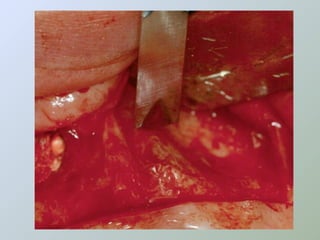

Acesso ao

Acesso ao periápice

• Freqüentemente o

osso cortical sobre o

ápice é reabsorvido

expondo uma lesão de

tecido mole

• Ampliar a abertura óssea

• Cinzel

• Broca esférica cirúrgica

• Expor a raiz e boa parte da

lesão

• Irrigação abundante

• Solução fisiológica

• Exposição óssea suficiente

para permitir boa visualização